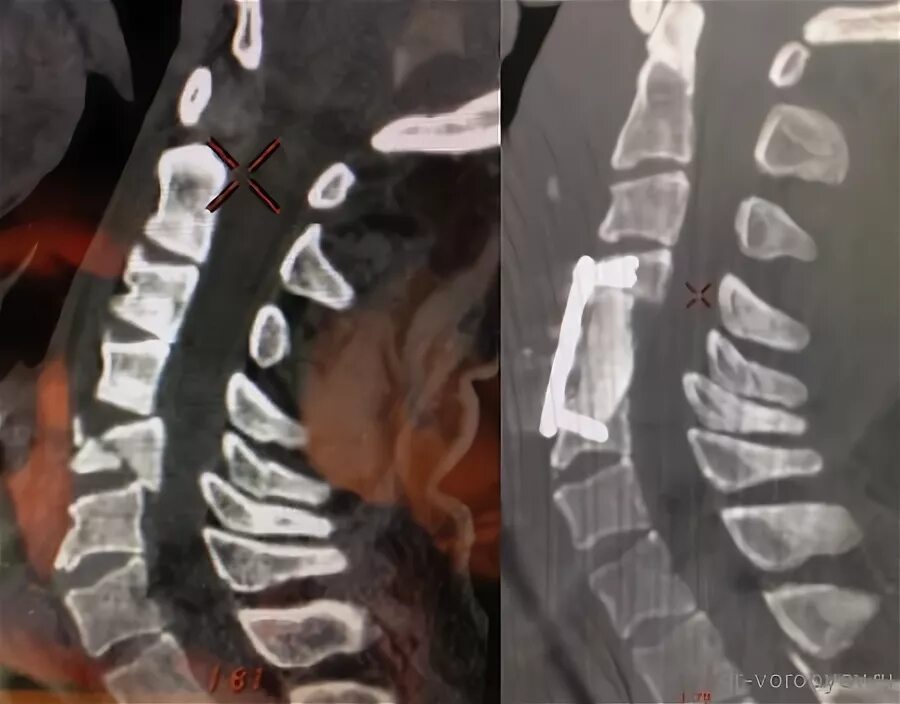

Стабилизирующие операции на позвоночнике